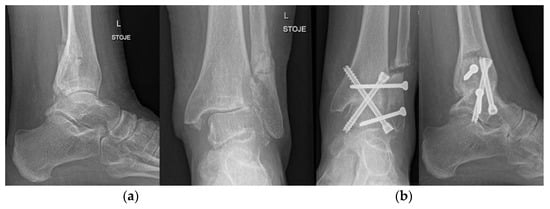

4.7. Ankle and Foot

- Duan, X.; Yang, L.; Yin, L. Arthroscopic Arthrodesis for Ankle Arthritis without Bone Graft. J. Orthop. Surg. 2016, 11, 154. [Google Scholar] [CrossRef] [PubMed]

- Cottino, U.; Collo, G.; Morino, L.; Cosentino, A.; Gallina, V.; Deregibus, M.; Tellini, A. Arthroscopic Ankle Arthrodesis: A Review. Curr. Rev. Musculoskelet. Med. 2012, 5, 151–155. [Google Scholar] [CrossRef]

- Mangwani, J.; Afifi, H.; Faroug, R. Arthroscopic Ankle Arthrodesis—Surgical Technique. J. Arthrosc. Surg. Sports Med. 2021, 2, 135–140. [Google Scholar] [CrossRef]

- Duan, X.; He, P.; Fan, H.; Zhang, C.; Wang, F.; Yang, L. Application of 3D-Printed Personalized Guide in Arthroscopic Ankle Arthrodesis. BioMed Res. Int. 2018, 2018, 3531293. [Google Scholar] [CrossRef] [PubMed]